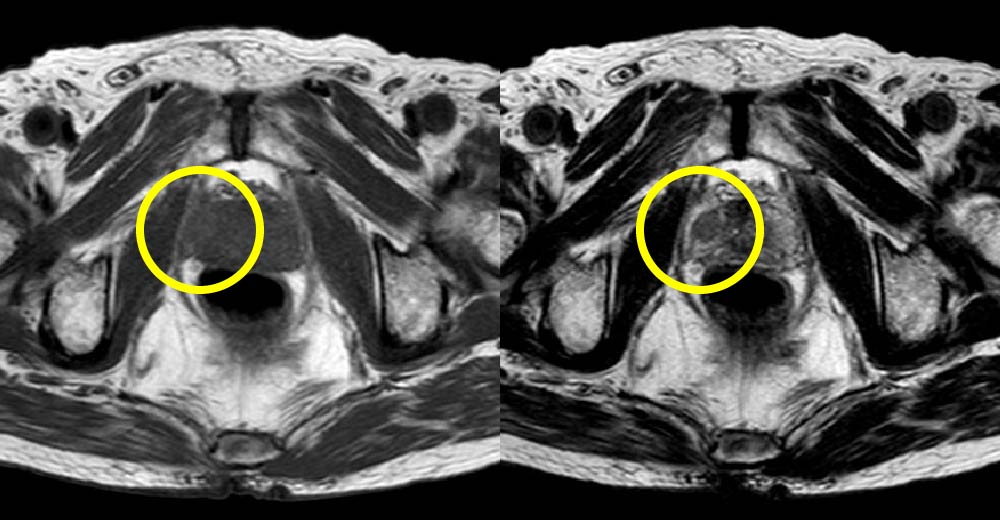

前立腺がん症例です。前立腺生検前にMRI撮影を行っています。

左:MRI T1強調 右:MRI T2強調